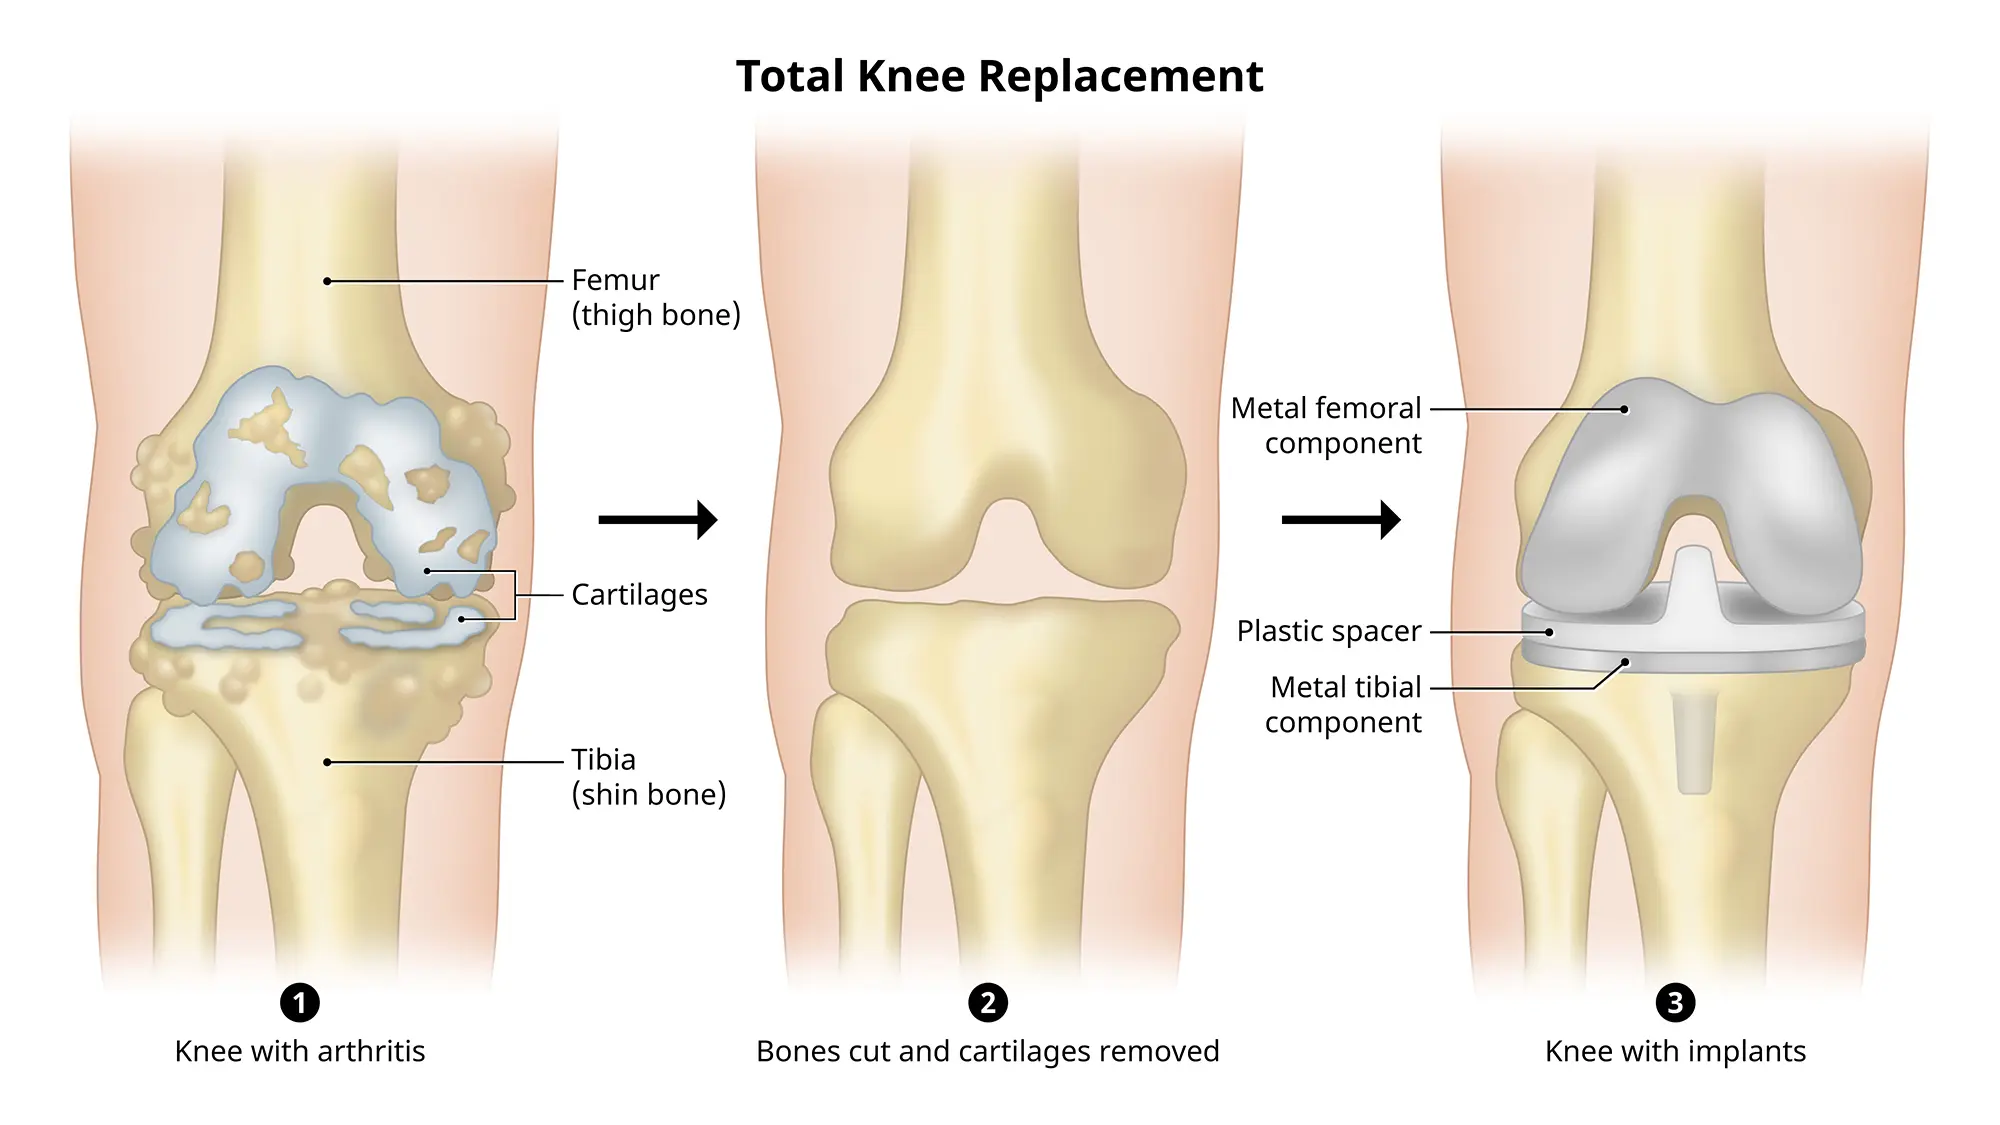

人工膝関節置換術 Total Knee Arthroplasty 全人工膝(ひざ)関節置換術(Total Knee Arthroplasty:TKAの詳細情報

全人工膝(ひざ)関節置換術(Total Knee Arthroplasty:TKA。COPYRIGHT UNION HOSPITAL 手術資料。Total knee replacement surgery (TKA) - Stock Illustration。人工膝関節置換術に関する専門的な内容を網羅した書籍。。关节置换术(膝关节置换)| 伊丽莎白医院。- タイトル: 人工膝関節置換術- サブタイトル: Total Knee Arthroplasty- 出版社: 南江堂- 定価: 1800円ご覧いただきありがとうございます。